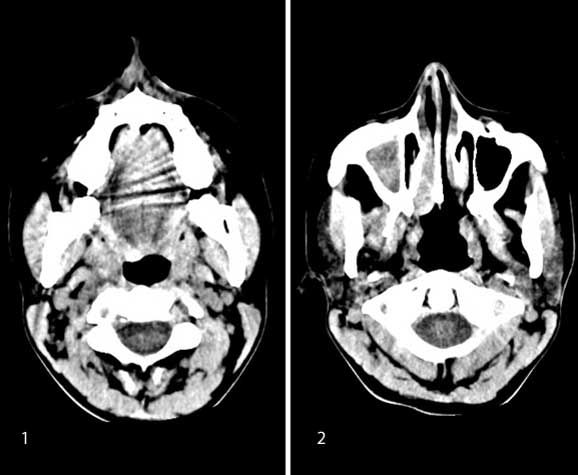

Case history: A 35-year-old patient with history of unilateral nasal obstruction.